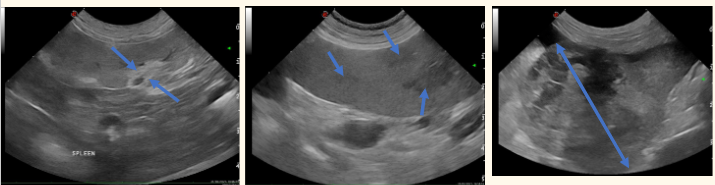

what are these 3 common findings in the spleen [during ultrasound]?

-myelolipomata

-nodular hyperplasia/extramedullary haematopoiesis

-splenic HSA